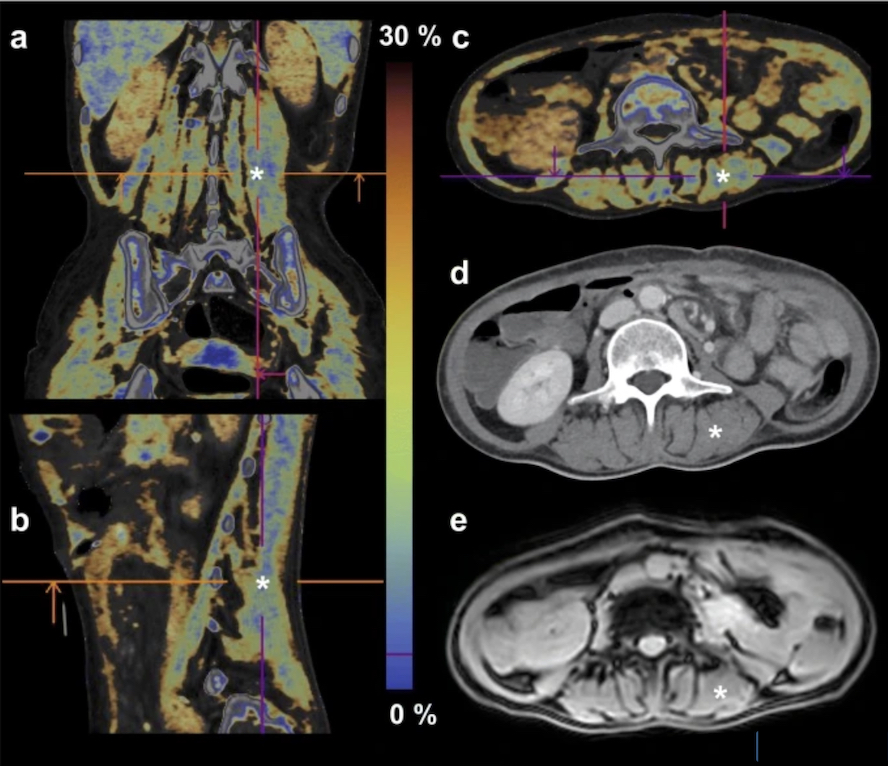

L'objectif principal d’une étude allemande publiée dans European Radiology était de quantifier la graisse dans le muscle squelettique en tant que mesure de la qualité musculaire. La fraction de graisse (DECT-FF), déterminée par la décomposition du matériau, et les valeurs HU sur des images DECT virtuelles sans contraste (VNC) ont été mesurées dans 126 régions d'intérêt et comparées à la relaxométrie IRM par déplacement chimique (MRCSR). En outre, une association entre les valeurs DECT et les classifications de la sarcopénie basée sur les valeurs de seuil SMRA provenant du scanner classique non injecté a été étudiée.

Sur la base des valeurs de l’aire musculaire squelettique (SMA), l'indice musculaire squelettique (SMI) a été calculé en utilisant SMA [cm2] / hauteur [m]2. Le SMI en tant que paramètre de la quantité musculaire a été utilisé pour classer les patients comme sarcopéniques ou non sarcopéniques, selon trois systèmes différents basés sur des seuils, qui classent les SMI selon le sexe, ou, pour les patients masculins, qui prennent également en compte l'IMC, ou enfin qui classent le SMI selon le sexe, l'IMC et l'âge. AU final, la corrélation était excellente entre DECT-FF et MR-FF (r = 0,91), DECT VNC HU et MR-FF (r = - 0,90), ou entre DECT-FF et DECT VNC HU (r = - 0,98). La corrélation intraclasse entre DECT-FF et MR-FF était bonne, avec une différence moyenne de 0,15%. Aucune relation significative entre les classifications DECT-FF et SMI n'a, en outre, été observée.